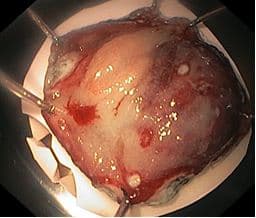

Резецированный участок слизистой оболочки растянут и закреплен булавками на пенопласте слизистой наверх, фиксирован в 10% растворе нейтрального формалина.

На рисунке: Резецированный участок слизистой оболочки, растянутый и закрепленный булавками на пенопласте слизистой наверх, фиксирован в 10% растворе нейтрального формалина.